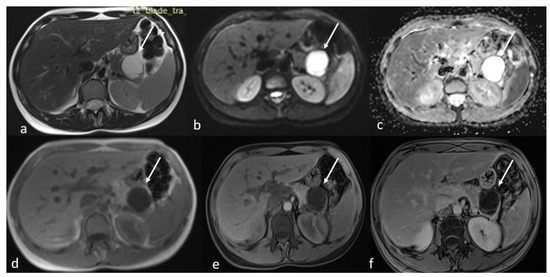

An MRI performed one year after the initial imaging and two months before admission revealed an increase in the size of the pancreatic cystic lesion to 4.5 cm (Figure 3 and Figure 4) with enhancement of its thin wall and internal septa, confirming its progressive nature. The lesion continued to compress the pancreatic tail and the greater curvature of the stomach, without causing pancreatic duct dilation. The imaging also showed low signal intensity on T1- and high signal intensity on T2-weighted sequences, with capsule enhancement post-contrast, suggesting a mucinous cystic neoplasm (Figure 4). Additionally, the MRI confirmed the presence of a 9 mm hemangioma and a small liver cyst, both unchanged from prior scans. No enlarged retroperitoneal lymph nodes were observed, and the MRCP findings showed normal intrahepatic bile ducts, common hepatic bile duct, gallbladder, and pancreatic duct. No abnormalities were found in the spleen, kidneys, or adrenal glands.

Figure 3.

(a,b) Axial sequences of the upper abdomen comparison showed an increase in the lesion size.

Figure 4.

Second MRI follow-up after 6 months showed an increase in the lesion size. (a) T2 Blade axial sequence showing hyperintensity of the cyst with no internal solid component. (b,c) DWI and ADC again showing no internal restriction of the cystic lesion. (d) T1 Vibe showing a hypointense cystic lesion at the tail of the pancreas. (e,f) T1 Vibe post-contrast at arterial and venous phases showing no change in the enhancement of the cyst.